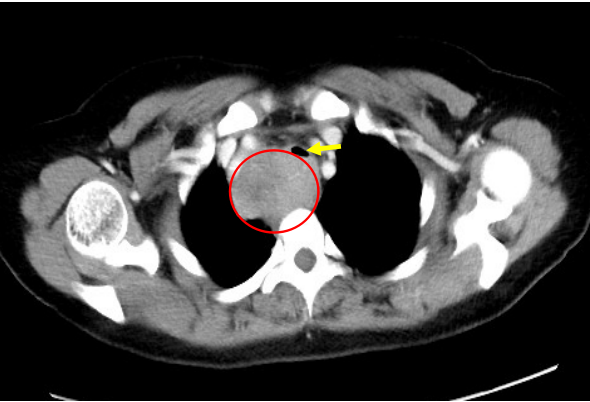

红圈內为肿瘤;黄色箭头为受压的气管

“必须尽快进行手术!”患者肿瘤由颈根部向下,紧贴气管延伸至心脏上方,向内压迫导致气管导致严重狭窄,患者出现了明显憋喘症状。胸外科副主任、主任医师陈东红介绍到,“这种情况对麻醉是个挑战,气管插管困难可导致患者窒息甚至死亡。并且,术中如果发现肿瘤侵犯气管,需要进行气管切除重建。如果肿瘤侵犯右侧头臂干动脉,还需要进行大血管切除重建。”